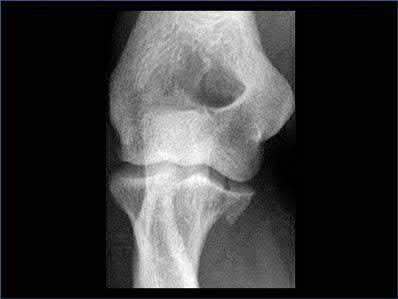

A 34-year-old male falls from a roof and sustains a right elbow dislocation that is closed reduced in the emergency room. An AP radiograph is shown in Figure A. This injury pattern is at highest risk for which of the following?

Anteromedial coronoid facet fracture and LCL injury following an elbow dislocation is commonly associated with varus posteromedial rotatory instability. Varus and posteromedial rotation force on the forearm results in rupture of the LCL from its humeral origin. As the LCL ruptures, the medial coronoid process is fractured as it impacts against and under the medial trochlea. Fracture involvement of the sublime tubercle, where the MCL attaches, can lead to more instability. Ulnar neuropathy can be seen following this injury pattern but AIN and PIN nerve palsy do not commonly characterize this injury pattern.

The review article by O'Driscoll highlights key points in diagnosis and management of capitellum, distal humerus, coronoid, and terrible triad injuries.

The article by Doornberg and Ring is a Level 4 study of 18 patients that sustained varus posteromedial rotational injuries resulting in anteromedial facet coronoid fractures. They found that lack of fixation at injury or malunion of the anteromedial facet were significant predictors of suboptimal functional outcome and development of arthrosis.

The anteromedial facet is highlighted in yellow as displayed in Illustration A. Illustration B depicts the lateral collateral ligament injury also evident during

varus stress fluroscopic examination, due to tension failure of the LCL off its humeral origin during the various mechanism.